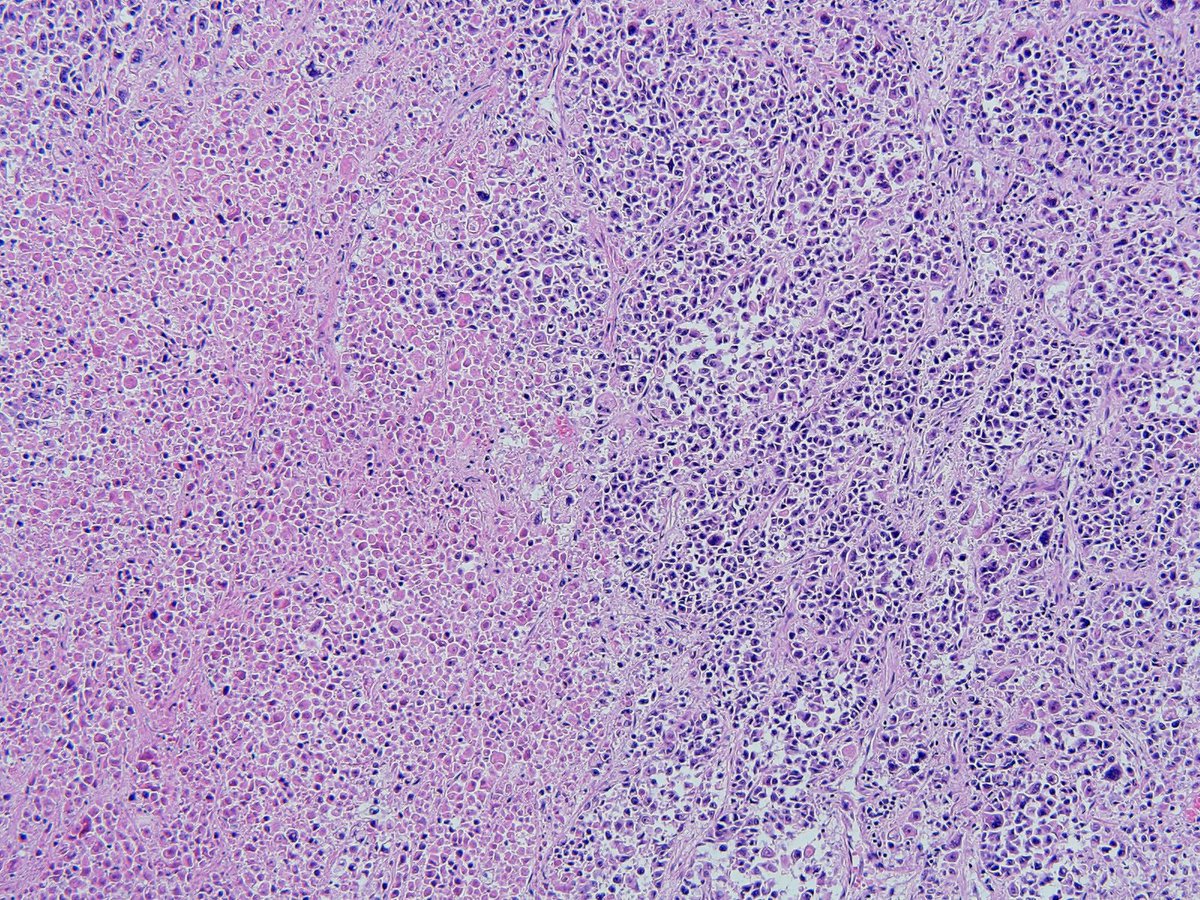

Мостовидный некроз

Мостовидный некроз 103 фото